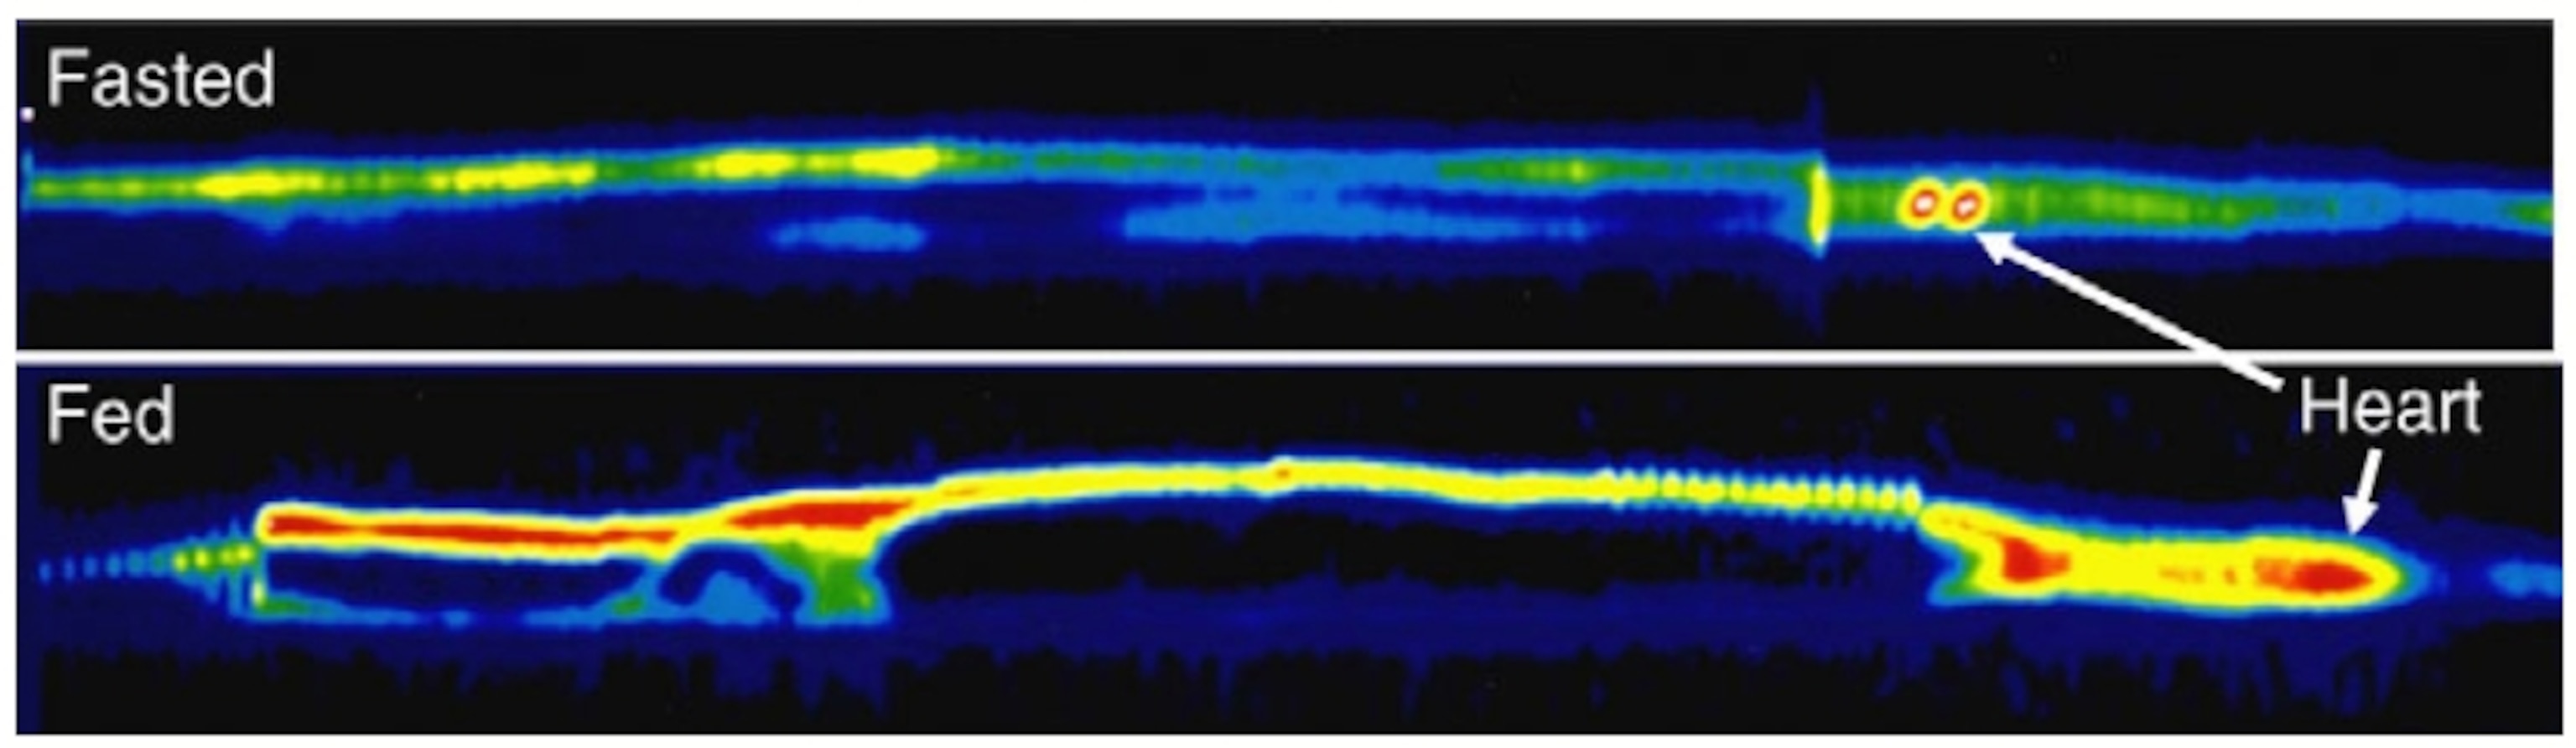

Here’s an image from one of Sekor’s later studies, showing glucose levels (red and yellow) in a hungry animal (top) versus a just-fed one (bottom):

So the python gut expands rapidly after eating, just as Stylopoulos showed happens in the rat gut after bypass surgery. But “what is really amazing,” Stylopoulos said, is that the python gut also sees a surge in glucose metabolism after being fed.

The difference between the python model and the bariatric surgery model is that for pythons, the gut goes back to normal once the food is gone. With surgically treated rats, in contrast, the gut expansion doesn’t seem to go away, presumably because the undigested food keeps on coming.